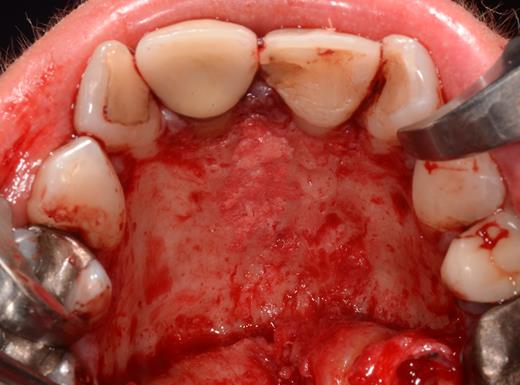

After a sulcular incision on the palatal side from teeth 15 to 25 and an incision in the midline of the palate omitting the incisive papilla and the two orifices of the NPD, two full-thickness mucoperiosteal flaps were raised. Thereafter, the incisive papilla and the whole contents of the incisive canal were enucleated (Figs 4–6). The bony incisive canal was filled with autologous bone harvested from the palatal region (bone scraper) (Fig. 7). A tension-free primary wound closure was achieved by moving the palatal flaps to the midline using single button and interdental vertical mattress sutures (Monocryl 4-0, Ethicon, Johnson & Johnson, USA) (Fig. 8). To avoid wound dehiscence and hematoma, an iodoforme gauze and a palatal plate were applied (Fig. 9). The patient was instructed to rinse three times a day with 0.1% chlorhexidine (formula hospitalis) for 2 weeks postoperatively. Sutures were removed after 14 days.

Filling of the incisive canal using autologous bone harvested from the palatal region.